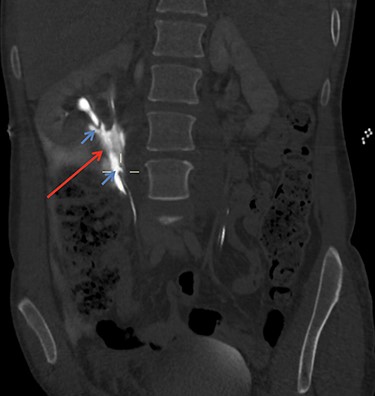

On arrival at 02:00, her temperature was 40.3°C with stable vital signs. After assessment by a multidisciplinary trauma team (orthopaedics, general surgery and urology), she had a CT Urogram that showed duplex kidneys and extravasation of contrast within the right peritoneum in keeping with urine leak (Figs 1 and 2). The lower moiety ureter was discontinuous with a mildly thickened and hyper-enhancing wall. The area of discontinuity was related to the highest density fluid on urographic phase, in keeping with this being the source of urine leak. The right upper moiety ureter appeared to be intact. There was no concomitant parenchymal injury.

CT Urogram demonstrating extravasation of contrast. The blue arrows show the severed ends of the right inferior collecting system. The red arrow shows the contrast extravasation.